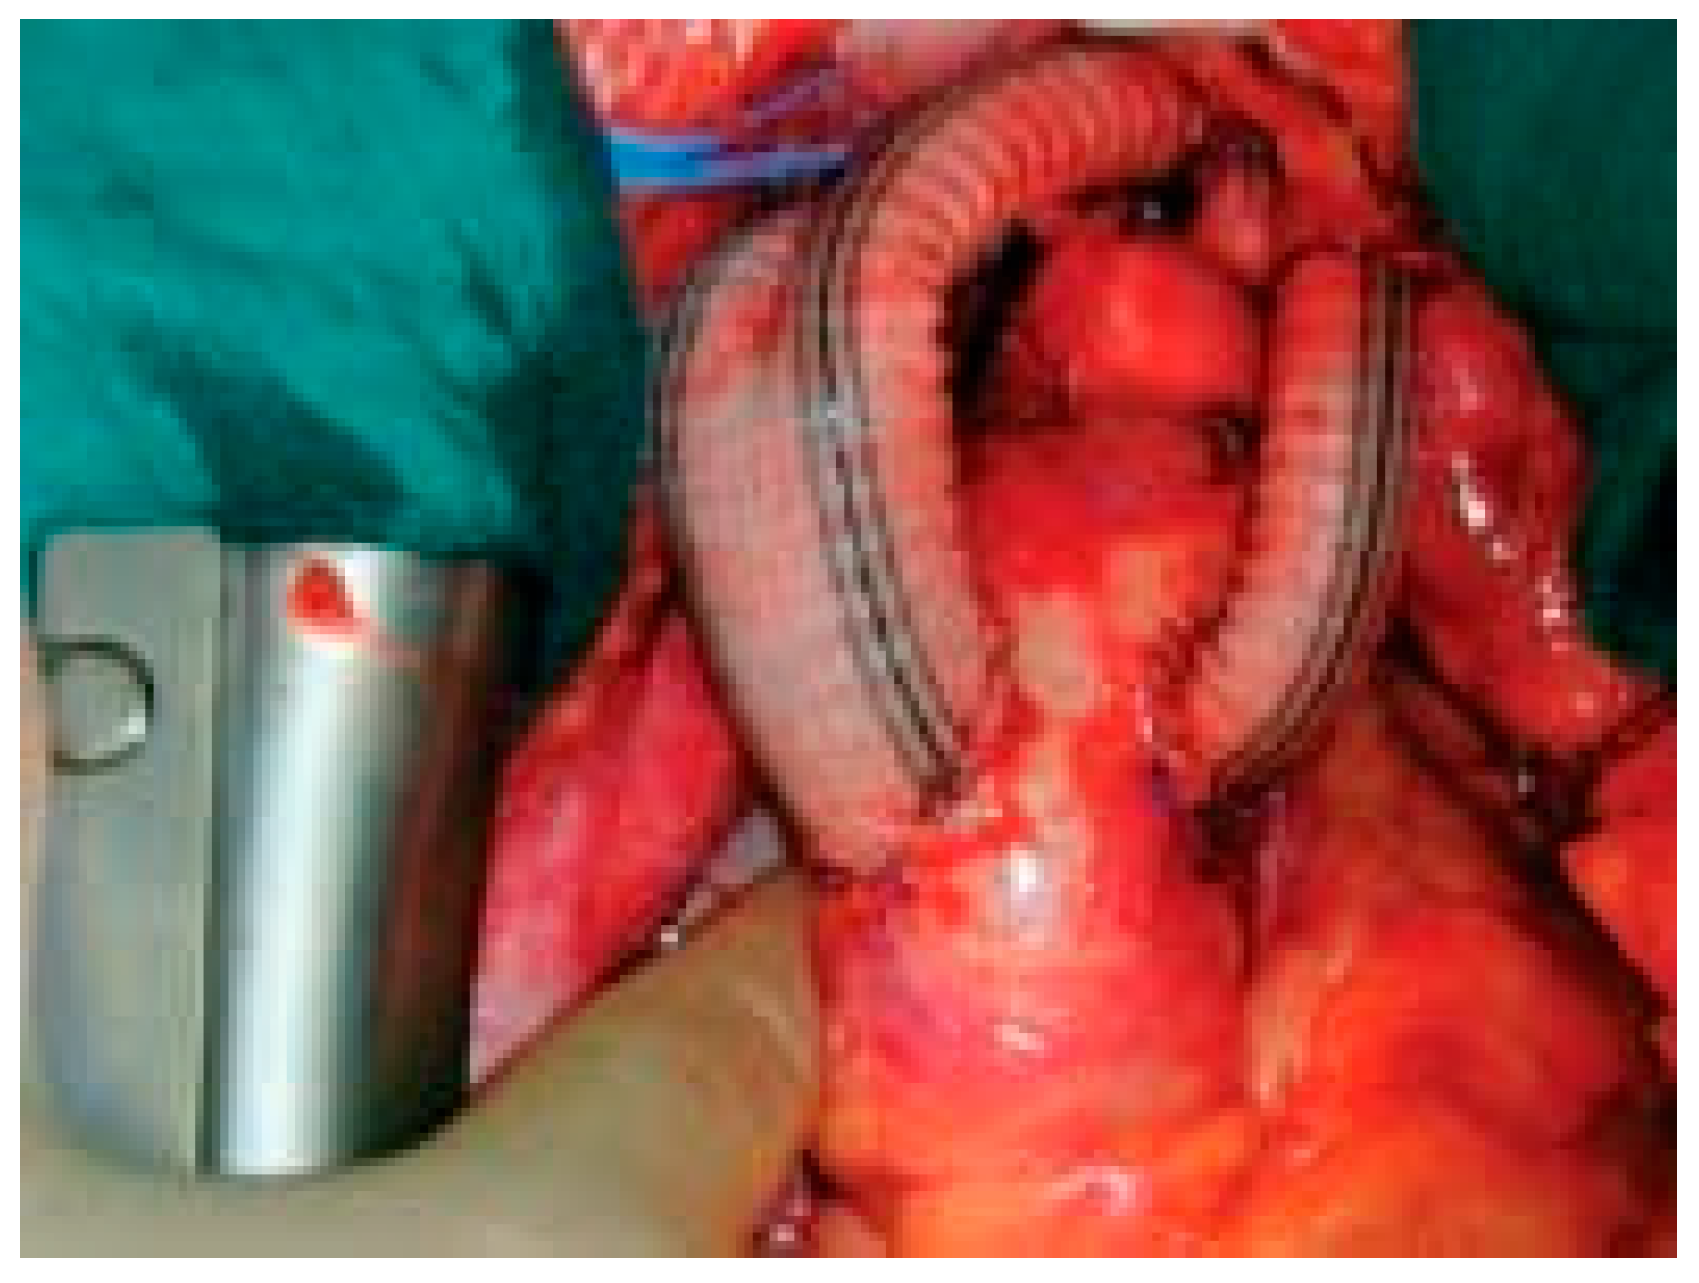

Figure 4.

Intraoperative view at the end of the procedure.